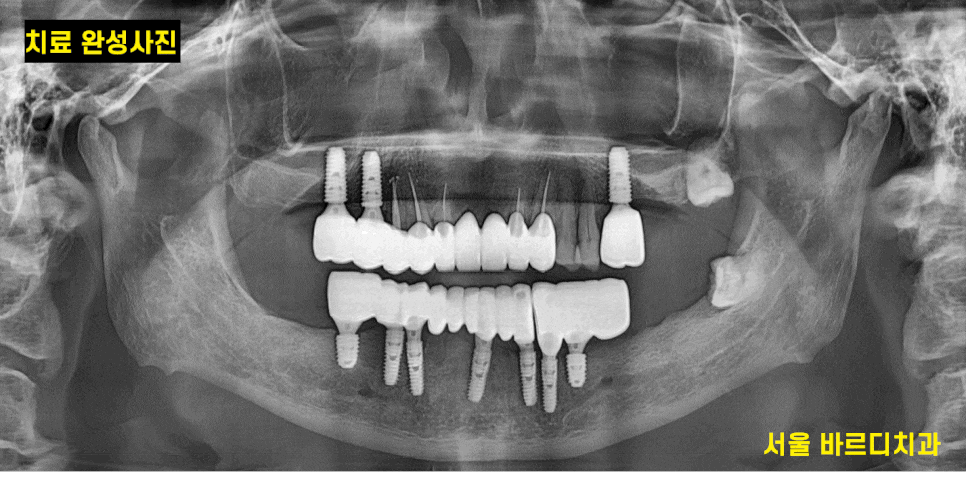

치료 후 사진입니다.

하악 전체 임플란트 7개로 12개의 머리를 완성

상악도 3개의 임플란트 치료를 진행했습니다.

약 5개월정도 치료 기간이 걸렸습니다.